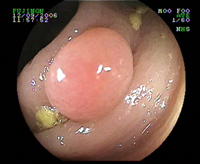

Gros polype pédiculé